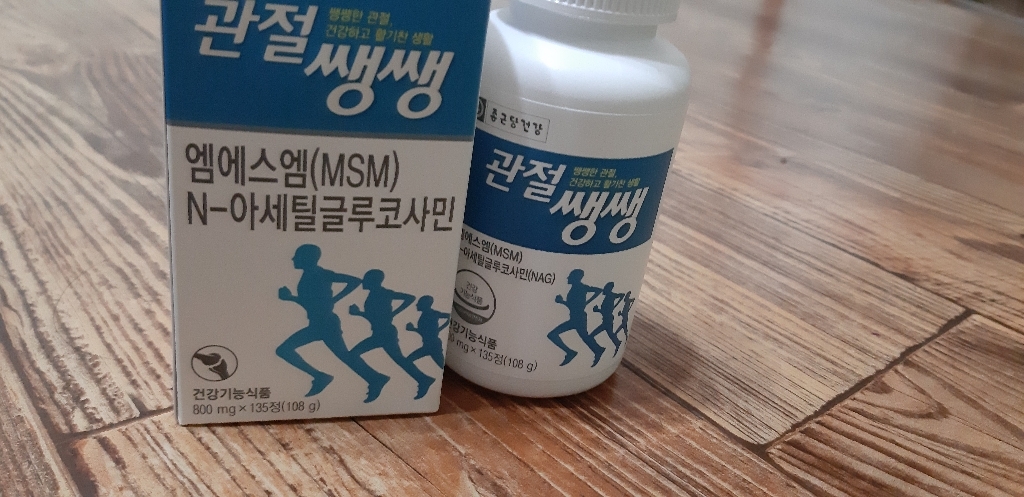

종근당건강 관절쌩쌩 글루코사민 무릎 관절 영양제 뼈에좋은영양제 보스웰리아 상어연골 초록입홍합오일 허리협착증 NA 아세틸글루코사민 s 관절영양제무릎이 아파서 지인의 소개로 종근당글루코사민 관절을 사서 지금까지 먹고 있는데 증상이 많이 좋아졌어 좋아요.엄마가 좋아해요.